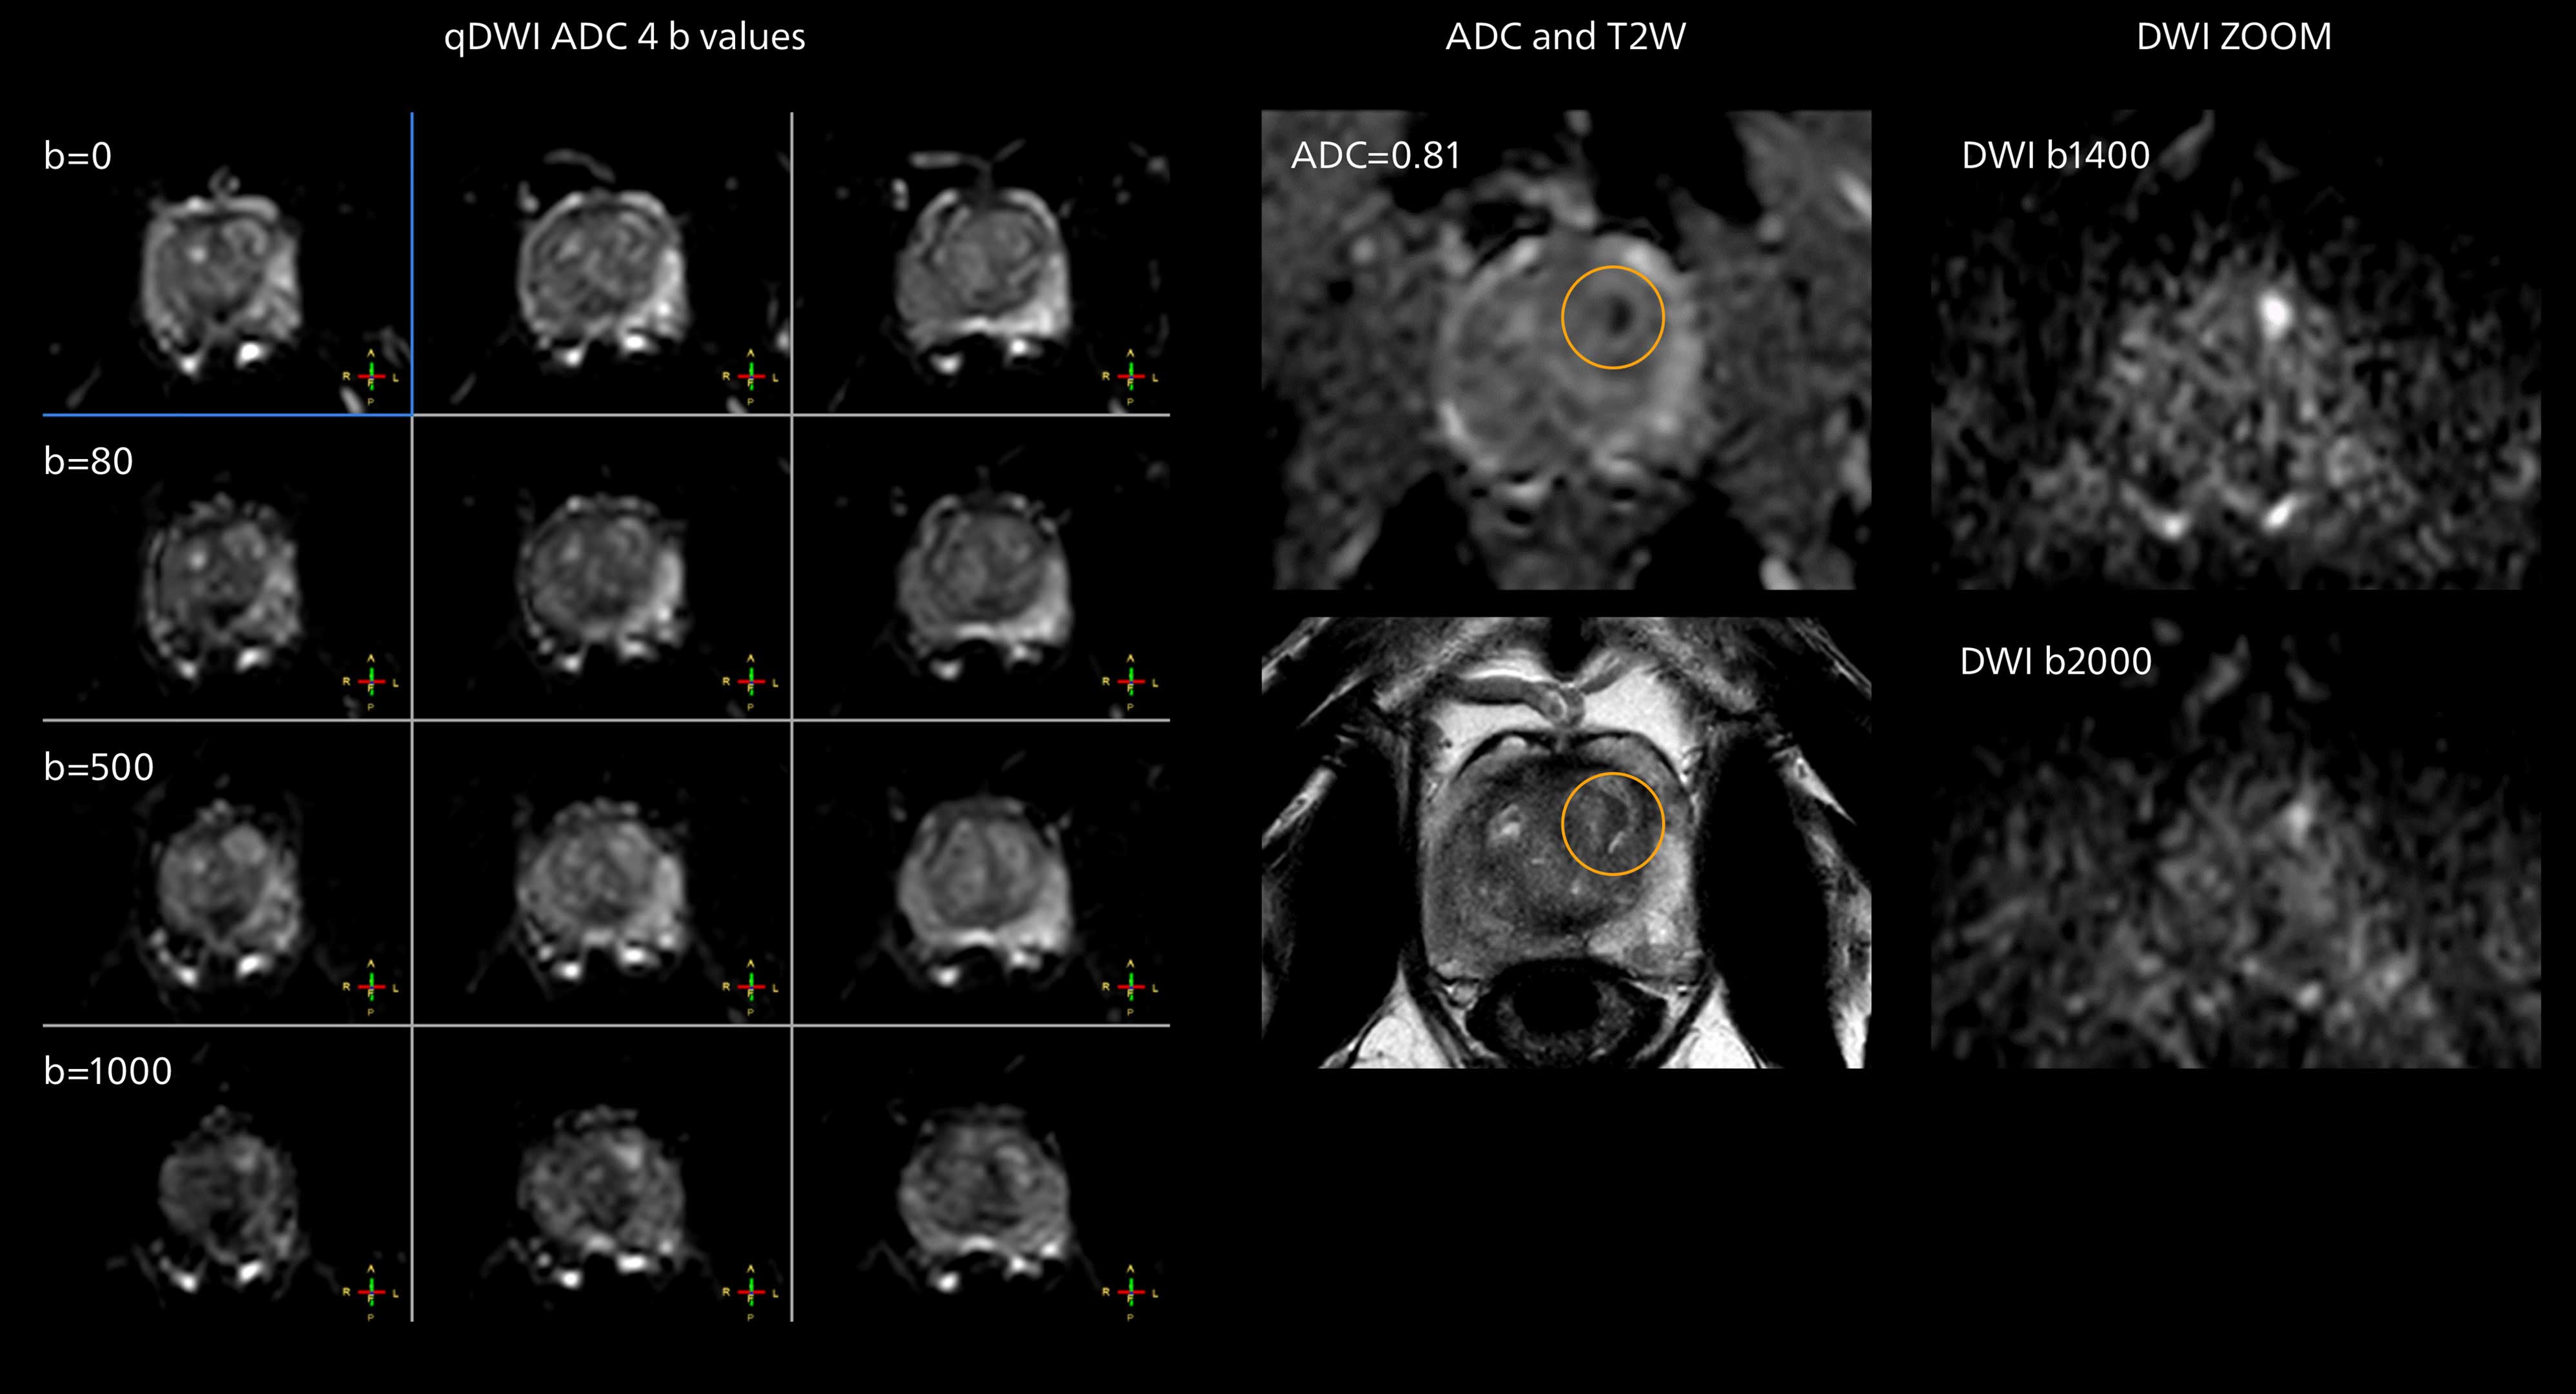

The examples on the left show the regular clinical diffusion protocol with four b-values up to b1000 s/mm². On the right, the T2W image shows a hypointense lesion that has low ADC and is clearly visible in b1400 and b2000 diffusion images, suggesting malignancy.